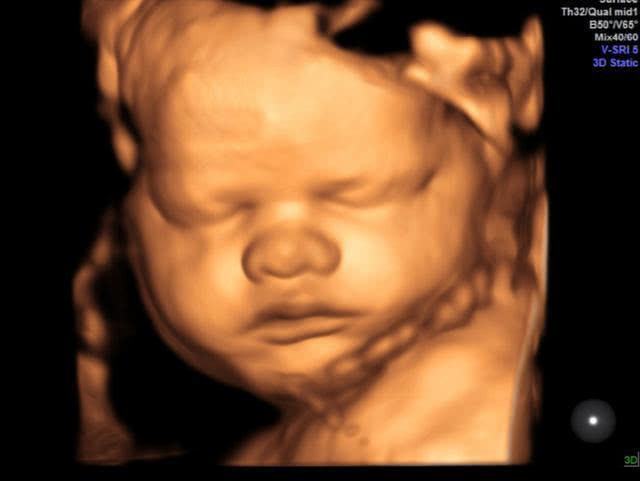

怀孕期间最重要的一项检查是大排畸检查,可以做三维彩超也可以做四维彩超。排畸检查都是绕不过去的检查,因为太重要了。

排畸检查可以查到胎儿的头面部、大脑、内脏器官、四肢、脊柱等外观是否正常,如果孩子有异常问题,需要孕妈妈们早做准备,别等到生下来再发现,到时候会给家庭带来精神和经济负担。